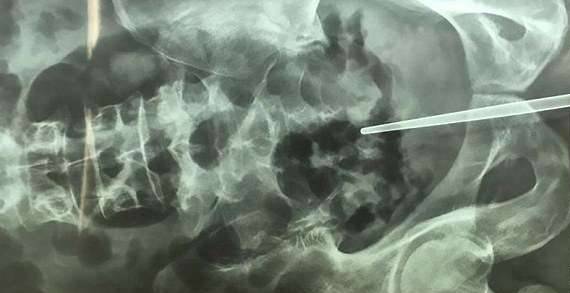

不久前,大陆杭州一名男子到医院就诊,称自己这几天肚子痛,小便困难。医生为他照X光,本来想看看他的泌尿系统是否病变,没想到竟然看到了难以置信的一幕。一根约18cm长的不鏽钢筷子直直插在牠的尿道中,看起来非常诡异。

▼他準备用筷子将尿道撑开,看看有没有断裂。没想到不锈钢筷子越塞越里面,最后竟然拔不出来。他终于意识到问题的严重性,慌忙来到医院。就诊时因为觉得难为情,他还是没有说出实情,直到拍片后,医生才发现真相。

▼医生表示,因为筷子位置靠里,只能通过手术取出。手术中,他们发现筷子从前列腺穿出,又从膀胱间隙穿出,把腹膜戳破,直到直肠壁才停下。幸好直肠没有破裂,如果筷子穿行过程中戳破大血管,甚至会引发大出血、休克,患者还有可能死亡。